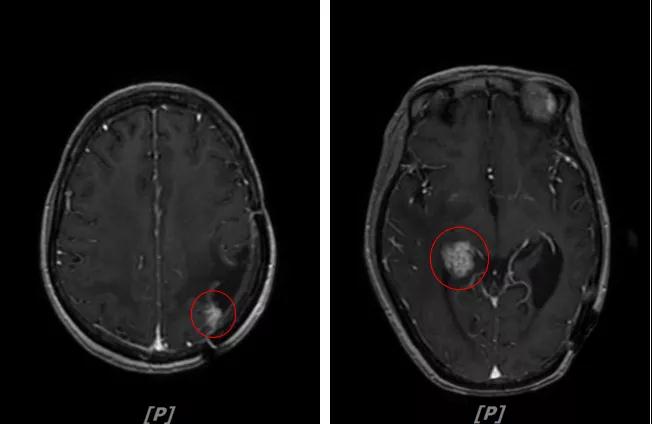

b.2014年3月全脑放疗结束后,予以LX方案治疗(拉帕替尼 1250mg qd+卡培他滨 1500mg bid)。每3个月规律复查,未见明显异常。下图为2014年6月患者行头颅增强MR检查,提示左顶叶脑转移瘤术后改变。

每3个月规律复查,未见明显异常。如2015年8月 头颅MR检查,提示:左顶叶脑转移瘤术后放疗后改变,对比前片2015年3月10日相仿。